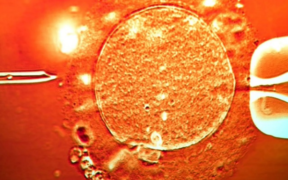

How a Man with a Cancer-Linked Gene Donated Sperm and Fathered 197 Children

An international investigation has revealed that a sperm donor carrying a dangerous cancer-linked genetic mutation unknowingly fathered at least 197 children across Europe. The findings, uncovered through a coordinated inquiry by 14 public broadcasters, show that some of the children conceived using his sperm have already died, while many others face a sharply increased lifetime